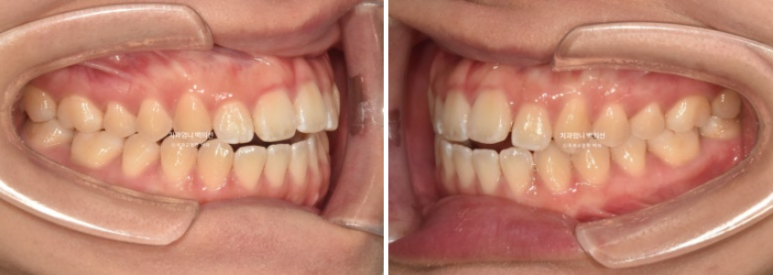

개방교합 뿐 아니라 철사의 변형으로 쓰러져 있던 송곳니도 세웠습니다.

24.12~25.06

원래 좋았던 교합은 잘 유지가 되었습니다.

6개월간 앞니 부분교정의 변화 치고 드라마틱 합니다.